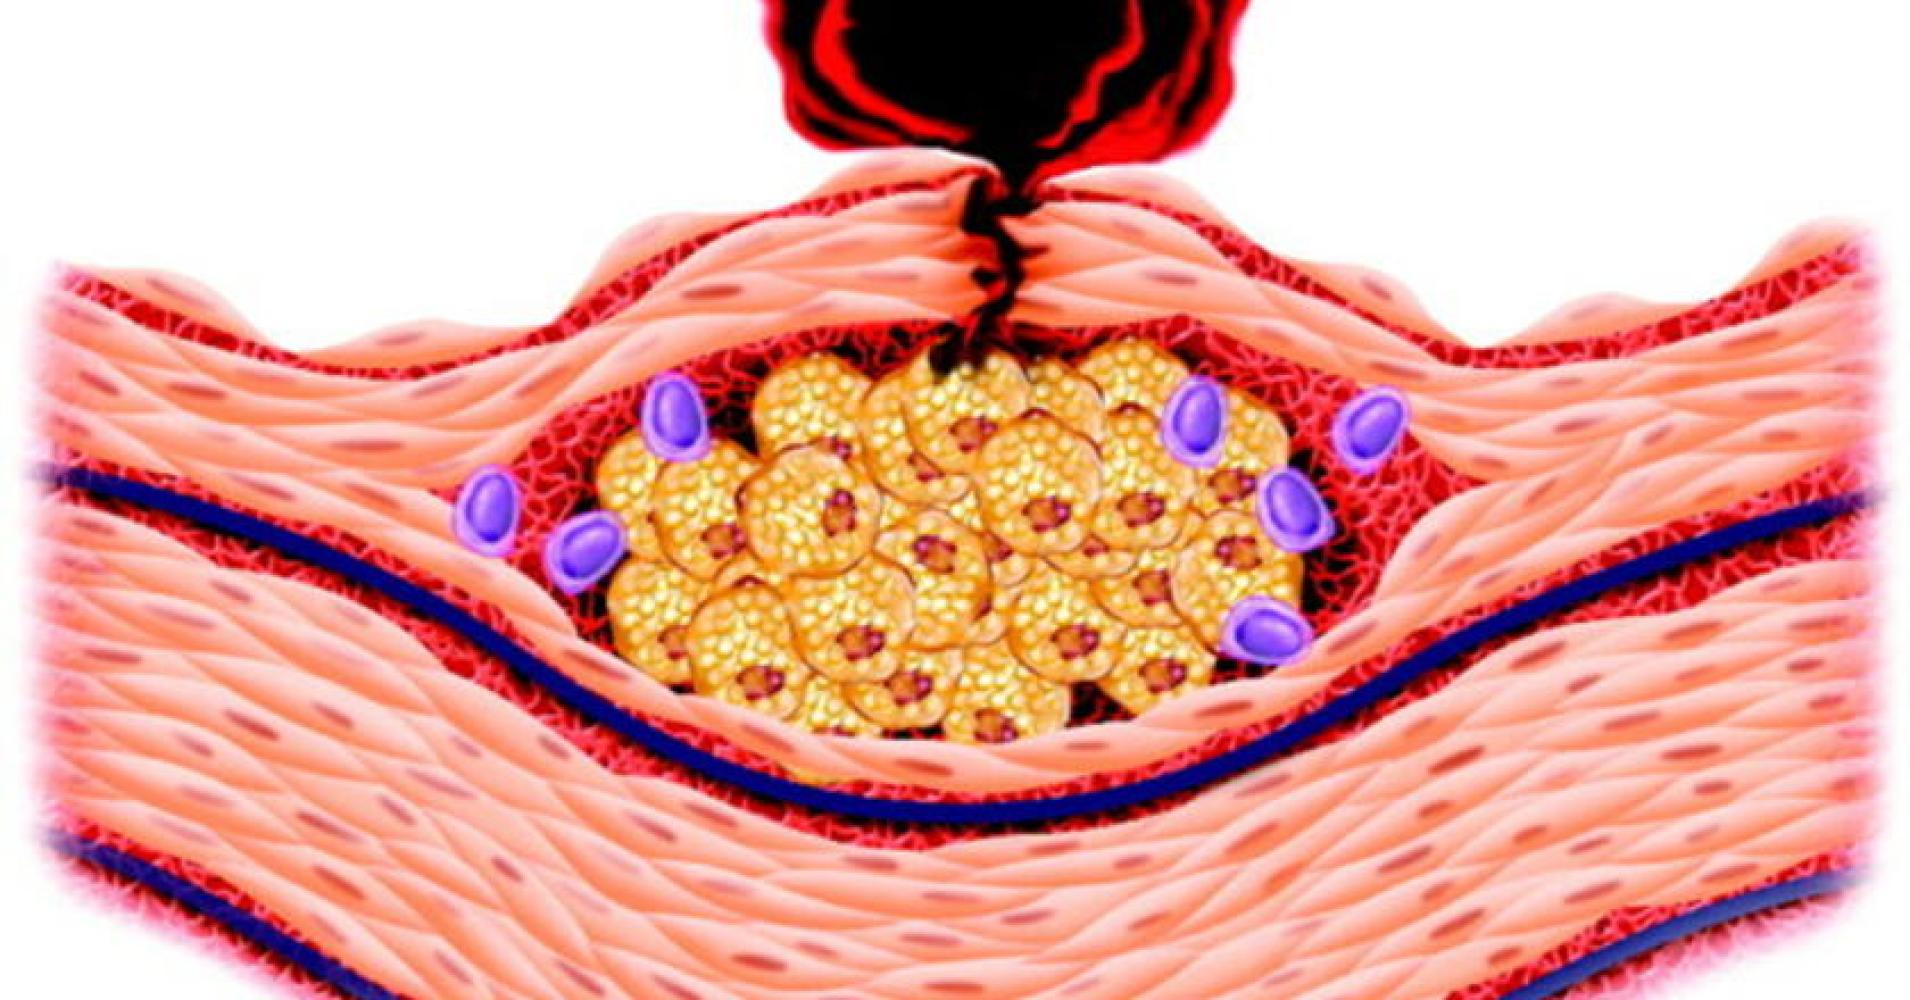

Воспаление бляшки

Воспаление бляшки 107 фото